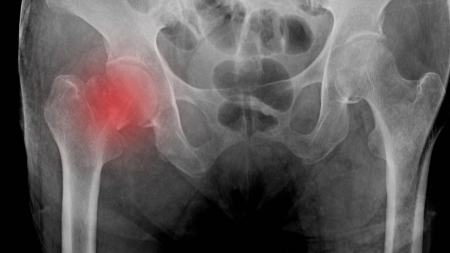

Debate: The 24 hour Time to Surgery Standard for Hip Fractures May Be Harming Patients.

Hip fracture care raises a key question: how fast should patients get to surgery? A large multinational RCT comparing accelerated surgery at about 6 hours to usual care showed no overall mortality benefit, but revealed an important nuance—patients with elevated troponins had dramatically lower 90-day mortality and fewer major complications when surgery was expedited. An observational meta-analysis of nearly 190,000 patients supported earlier treatment in general but suggested no added benefit when surgery occurred within 12 hours. Taken together, RCT methods provide stronger protection against confounding, making the accelerated 6-hour target more convincing for high-risk patients, while a 24-hour window remains reasonable for healthier individuals.